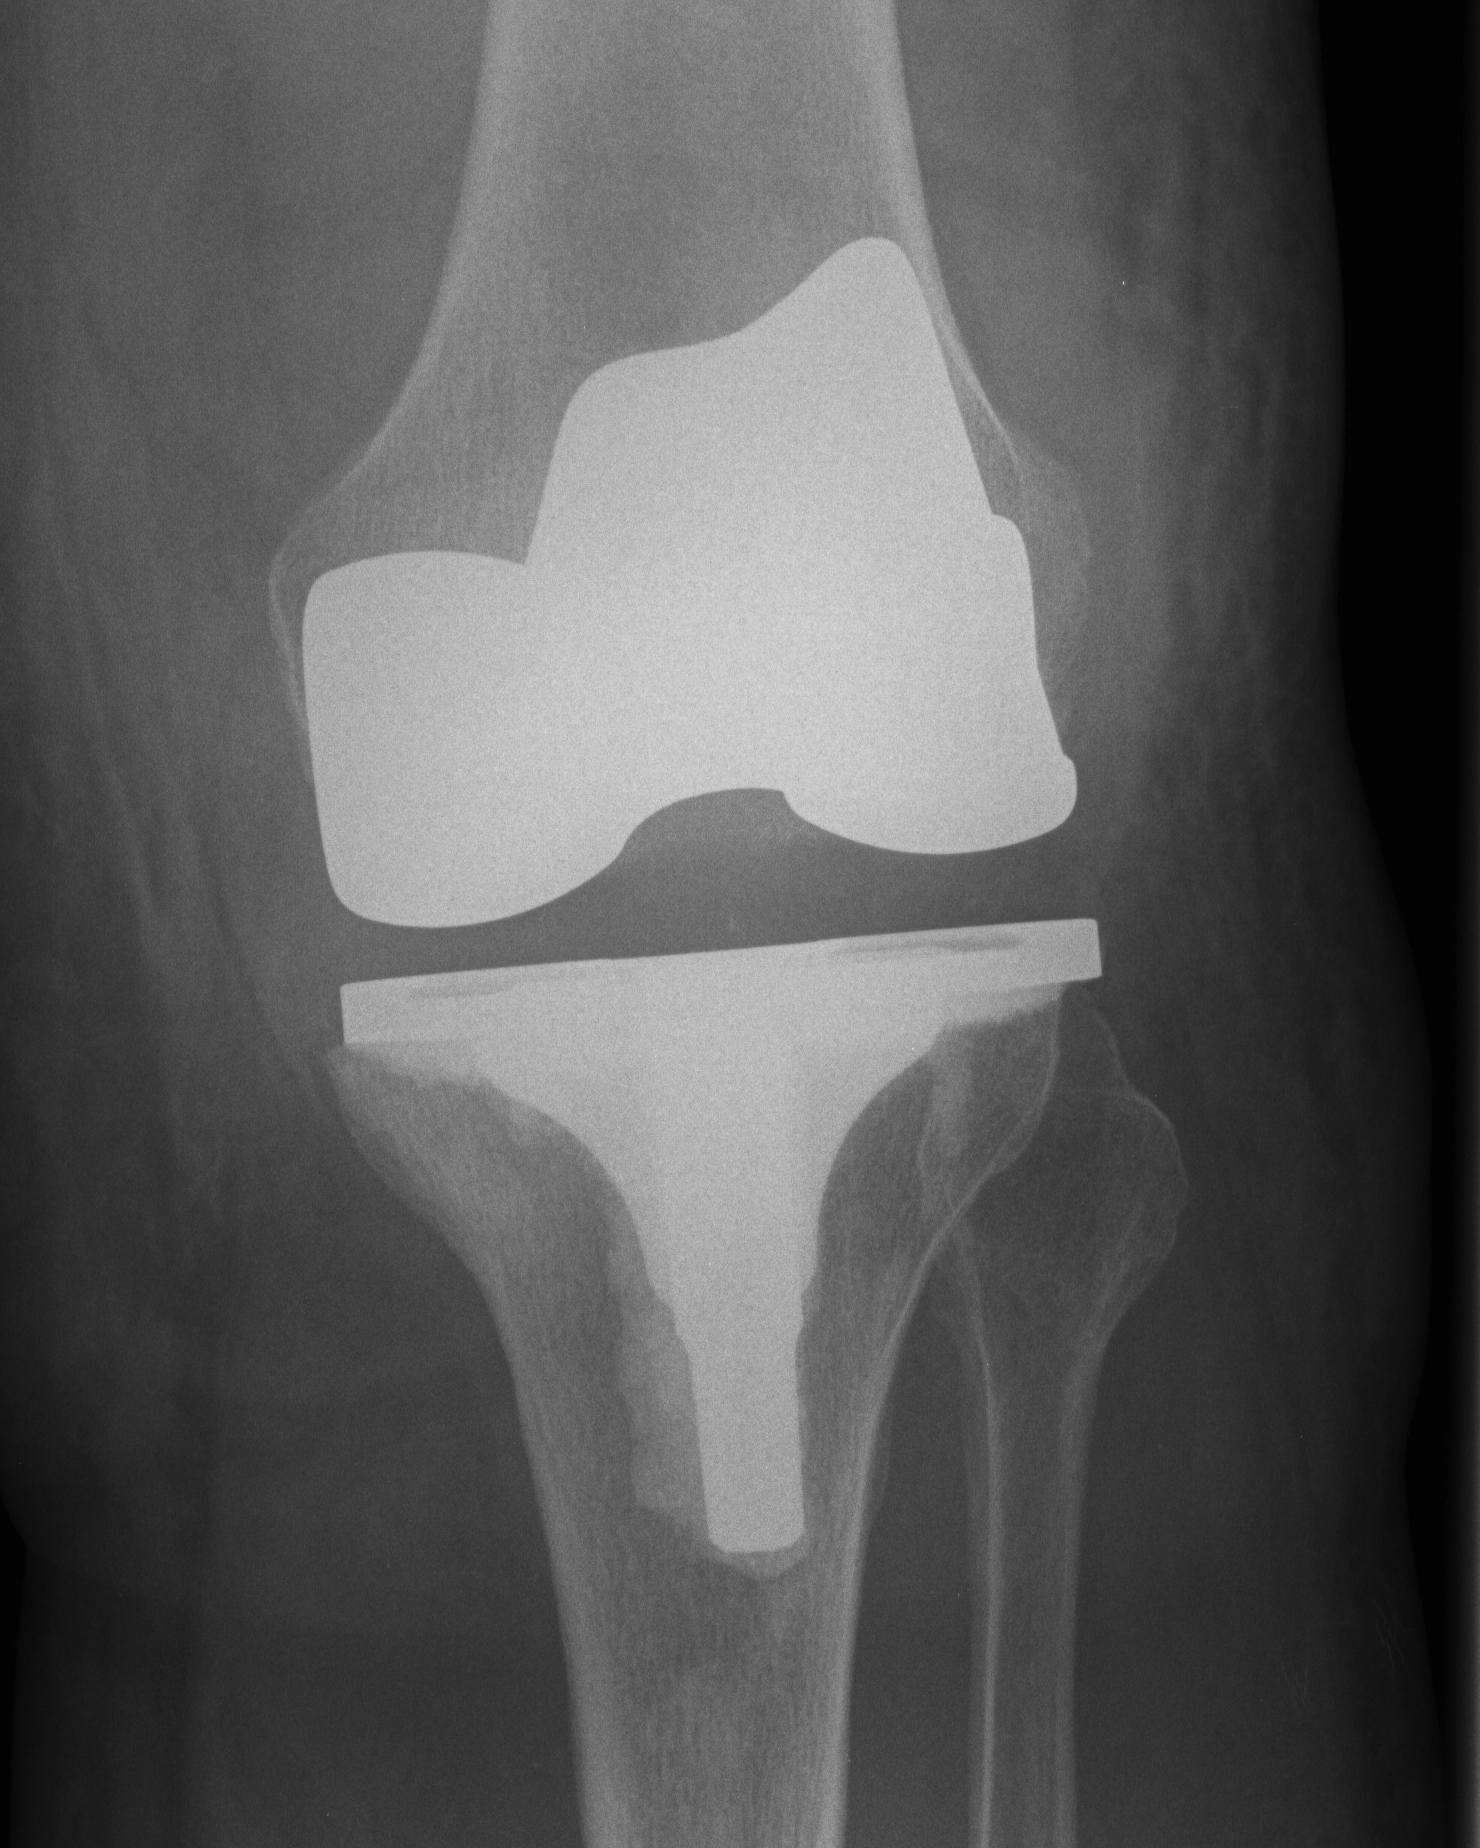

Correct alignment and soft tissue balancing

- two of the most important aspects of successful TKR

1. Restoration of mechanical alignment

- forces of the leg pass through the centre of the hip, knee and ankle

- allows optimal load share through medial and lateral sides of the prosthesis